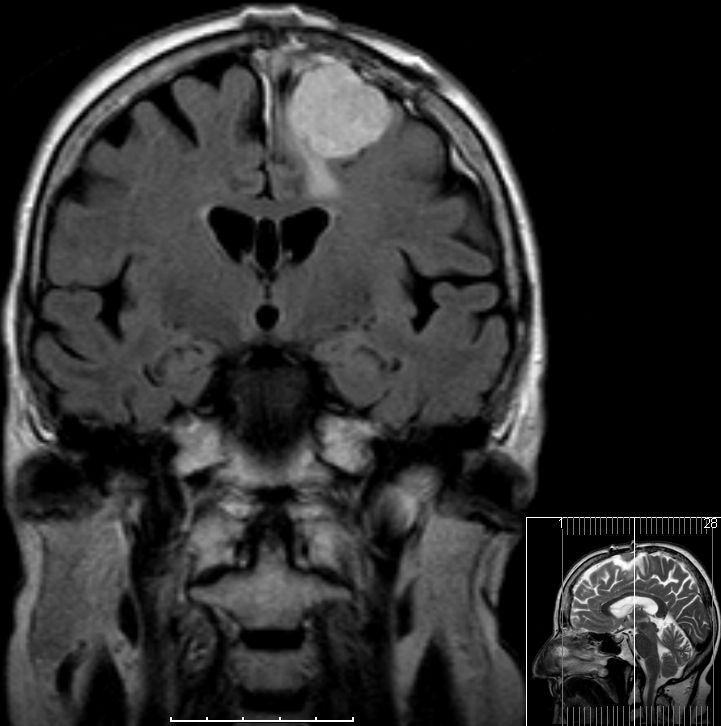

| zurück Home | Meningeom parietal | |||

72-jährige Patientin mit Teilparese des rechten Beins, passageren Sprachstörungen und Krampfanfall vor 6 Monaten. | |||

Postoperative Histologie: Meningeom Grad 1 | . | ||

Rezidiv 2 Jahre später. Postoperative Histologie: atypisches Meningeom II°![]() |